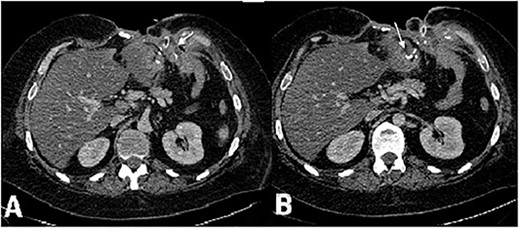

A CT of the chest, abdomen and small pelvis showed pulmonary embolism with no fresh focuses of infarct pneumonia, but revealed free fluid in the left pleural cavity, and atelectasis of the basal segment of the left lung, great defect of abdominal wall with the destruction of VIII-X ribs on the left side, multiple enterocutaneous fistulas, gastroatmospheric fistula formed by gastroenteric anastomosis leakage (Fig. 2), thrombosis of the left common femoral vein, hepatomegaly, liver steatosis, free liquid in the abdomen and small pelvis.

CT scan of the abdomen, axial view, venous phase. (А) Vast defect of the abdominal wall, distal gastric stump and (B) gastroenteroanastomosis leakage. Fistula opening in the wound in the left subcostal area.